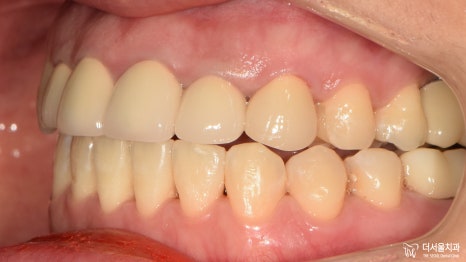

이전과는 달리 딱 봐도 고른 치열이 눈에 띕니다.

가지런한 치아와 상실된 기능 회복으로

만족, 대만족을 하셨던 환자분^__^

교정 과 임플란트 ,

둘의 합(合) 정말 놀랍지 않나요?ㅎㅎ

지금까지 20대 여성 교정 과 임플란트 ,

약 1년 반의 여정이었습니다.